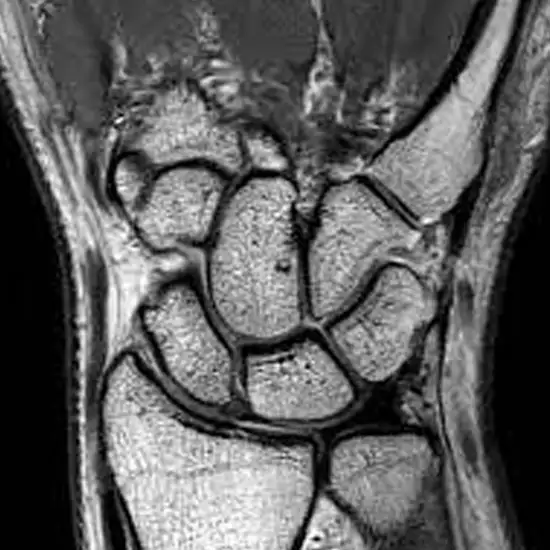

mri right wrist

An MRI of the left wrist joint visualizes the bones and associated soft tissues such as tendons, ligaments, muscles, and blood vessels.

These tests diagnose broken or fractured wrist bones and soft tissue injuries such as ligaments, tendons, and muscles.